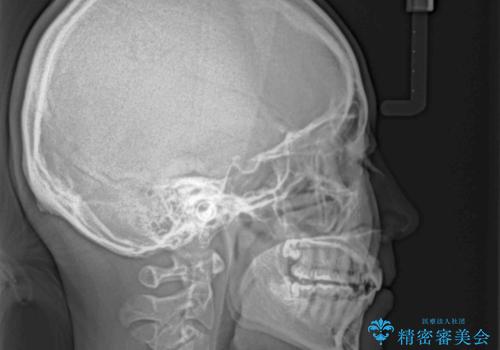

- 前歯のデコボコと突出感を気にして来院された患者様です。

上下左右第一小臼歯4本を抜歯して、積極的に口元を引っ込めるよう、ワイヤー装置にて矯正治療を行うこととしました。

口の閉じにくさが改善され、横顔のシルエットも大幅に改善されました。